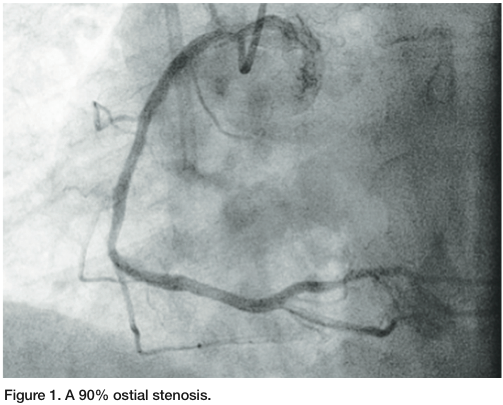

A 64-year-old female with history of coronary artery disease, previous stent of the ostial right coronary artery (RCA) and a previous mid RCA stent, presented with unstable angina symptoms. She underwent diagnostic angiography via the right radial artery with K. S. Chandrasekhar, MD. A 90% in-stent ostial restenosis of the RCA was found (Figure 1), as well as incomplete ostial coverage with the prior stent. The patient was referred for revascularization.